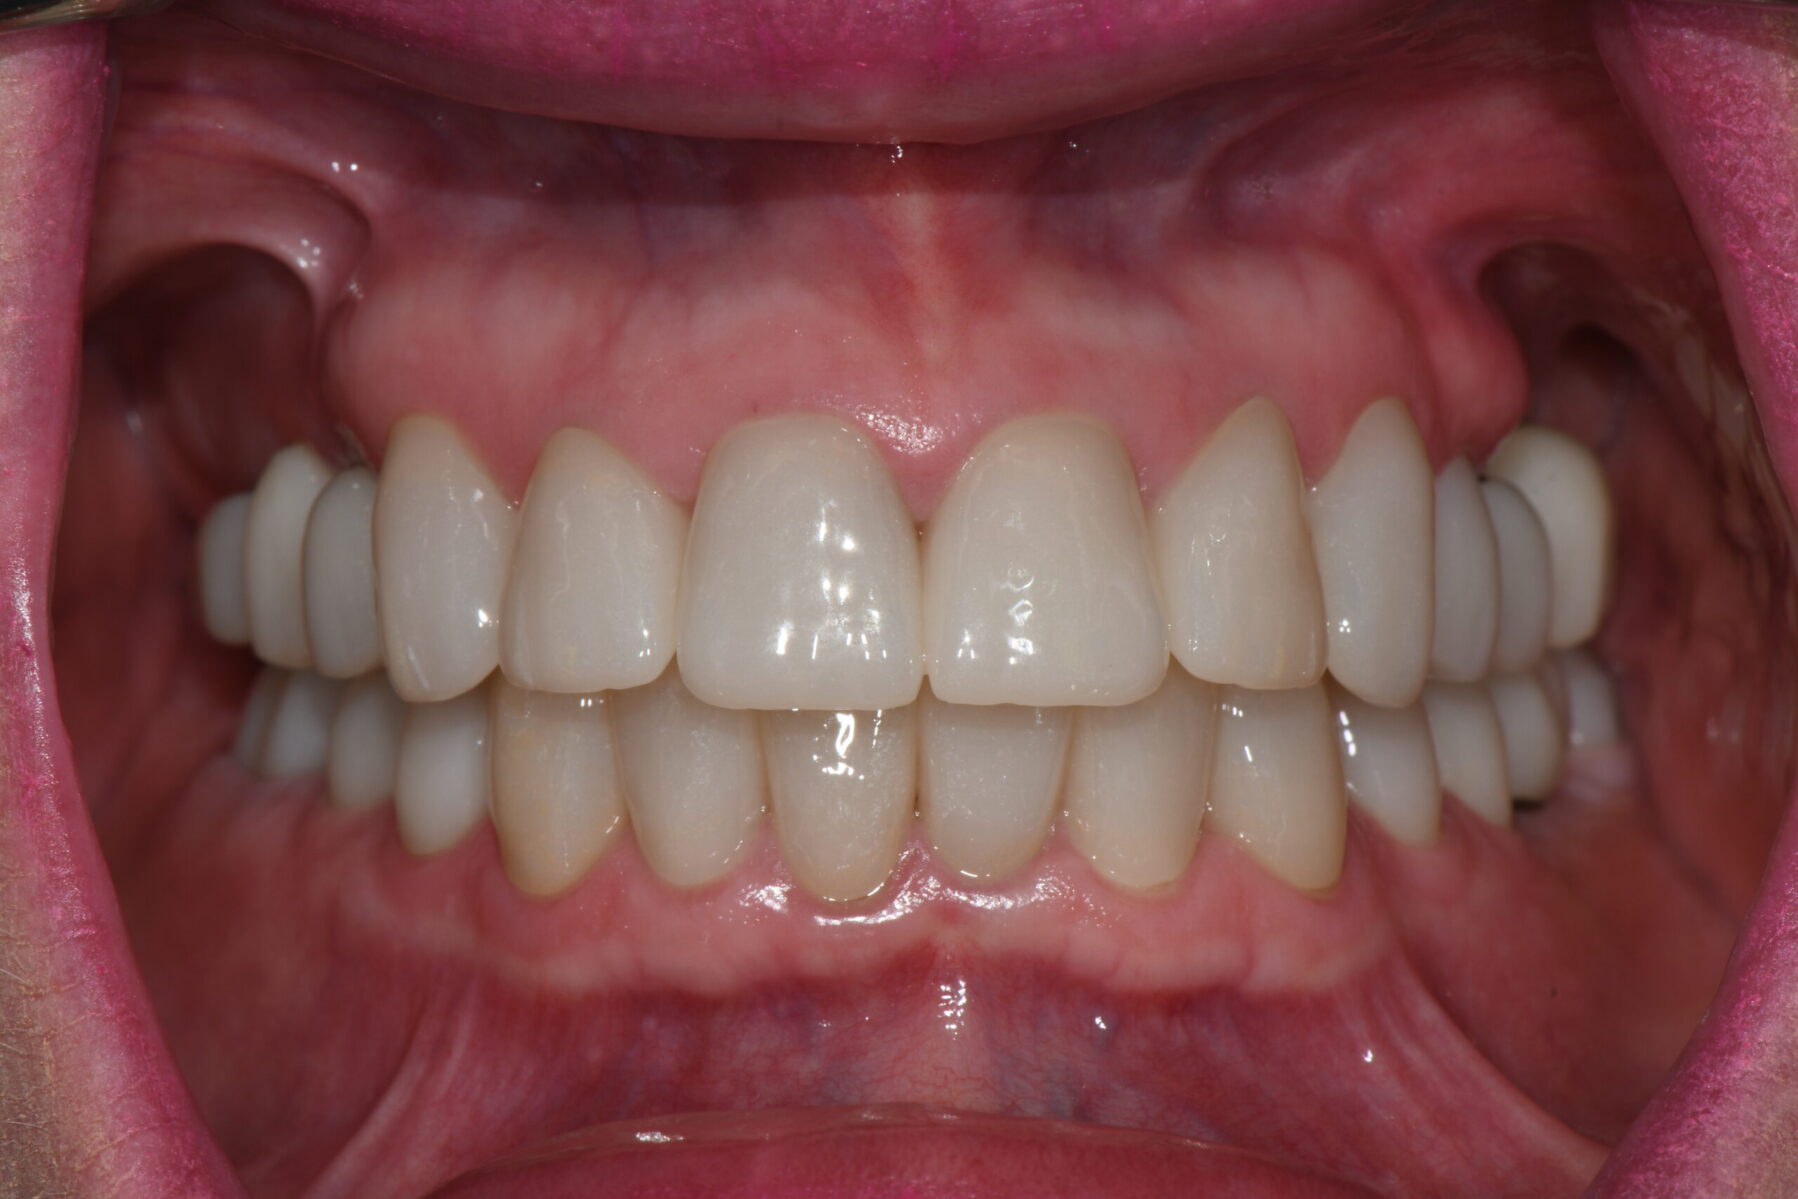

Full mouth rehabilitation encompasses a range of restorative dental procedures aimed at restoring the function, health, and esthetics of your entire mouth.

This may involve the use of crowns to protect and reinforce weakened teeth, dental implants to replace missing teeth, and veneers to improve the appearance of discolored or damaged teeth. Each treatment is tailored to match the color, shape, and size of your natural teeth, ensuring a cohesive and beautiful smile.